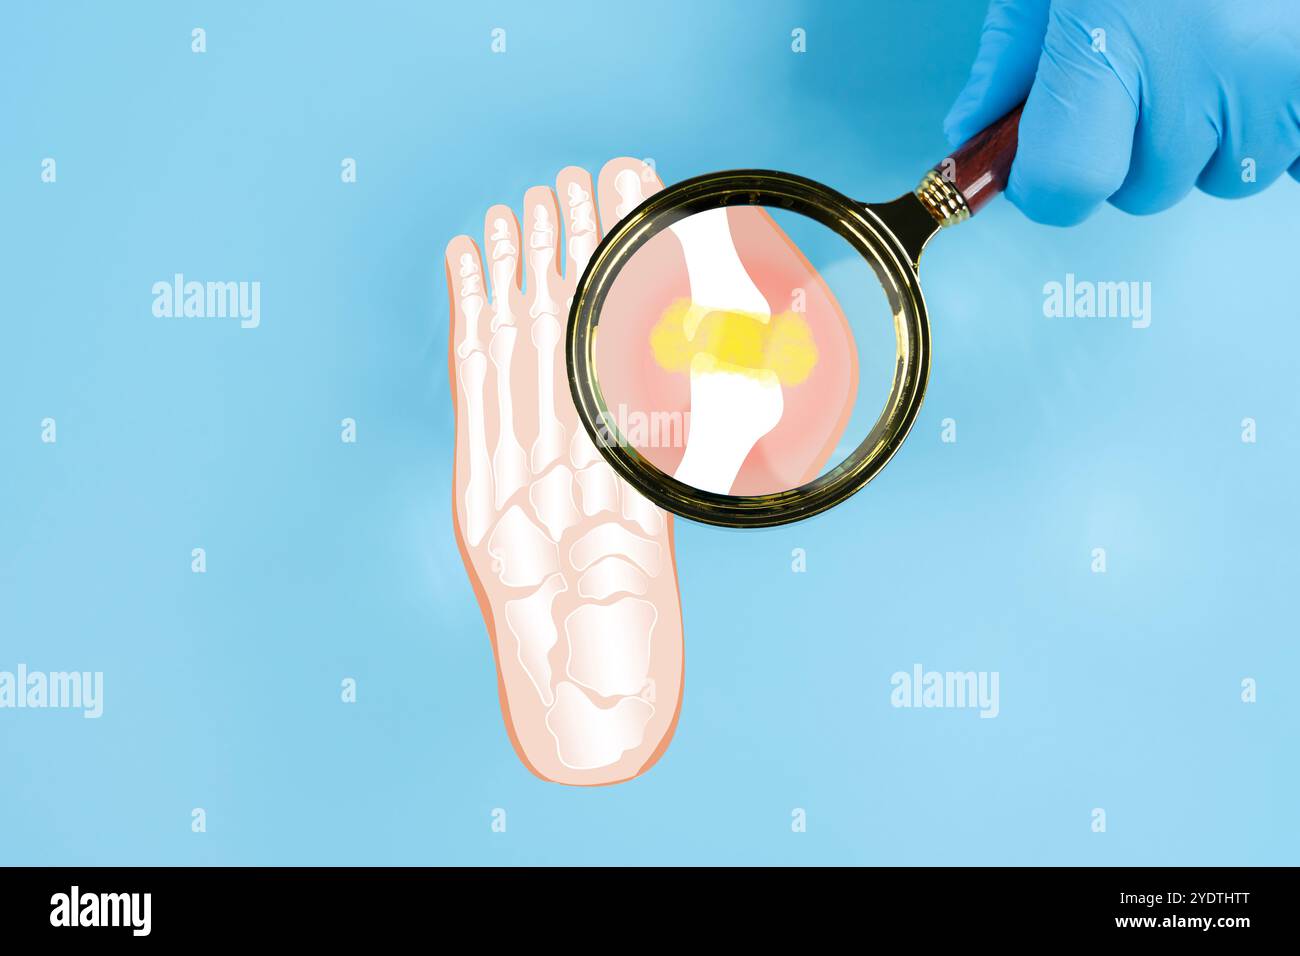

Gicht. Nahaufnahme des Gelenks mit entzündlicher Arthritis. Menschliche Fussskelettknochen durch Vergrößerungsglas isoliert, anteriore Projektion isoliert. Bildung Stockfotohttps://www.alamy.de/image-license-details/?v=1https://www.alamy.de/gicht-nahaufnahme-des-gelenks-mit-entzundlicher-arthritis-menschliche-fussskelettknochen-durch-vergrosserungsglas-isoliert-anteriore-projektion-isoliert-bildung-image628104638.html

Gicht. Nahaufnahme des Gelenks mit entzündlicher Arthritis. Menschliche Fussskelettknochen durch Vergrößerungsglas isoliert, anteriore Projektion isoliert. Bildung Stockfotohttps://www.alamy.de/image-license-details/?v=1https://www.alamy.de/gicht-nahaufnahme-des-gelenks-mit-entzundlicher-arthritis-menschliche-fussskelettknochen-durch-vergrosserungsglas-isoliert-anteriore-projektion-isoliert-bildung-image628104638.htmlRF2YDTHTE–Gicht. Nahaufnahme des Gelenks mit entzündlicher Arthritis. Menschliche Fussskelettknochen durch Vergrößerungsglas isoliert, anteriore Projektion isoliert. Bildung

Menschliches Fußskelett, gesehen durch eine oben isolierte Lupe. Medizinische Illustration für die Ausbildung. Gichtkonzept. Nahaufnahme des Gelenks mit Inflam Stockfotohttps://www.alamy.de/image-license-details/?v=1https://www.alamy.de/menschliches-fussskelett-gesehen-durch-eine-oben-isolierte-lupe-medizinische-illustration-fur-die-ausbildung-gichtkonzept-nahaufnahme-des-gelenks-mit-inflam-image628104648.html

Menschliches Fußskelett, gesehen durch eine oben isolierte Lupe. Medizinische Illustration für die Ausbildung. Gichtkonzept. Nahaufnahme des Gelenks mit Inflam Stockfotohttps://www.alamy.de/image-license-details/?v=1https://www.alamy.de/menschliches-fussskelett-gesehen-durch-eine-oben-isolierte-lupe-medizinische-illustration-fur-die-ausbildung-gichtkonzept-nahaufnahme-des-gelenks-mit-inflam-image628104648.htmlRF2YDTHTT–Menschliches Fußskelett, gesehen durch eine oben isolierte Lupe. Medizinische Illustration für die Ausbildung. Gichtkonzept. Nahaufnahme des Gelenks mit Inflam